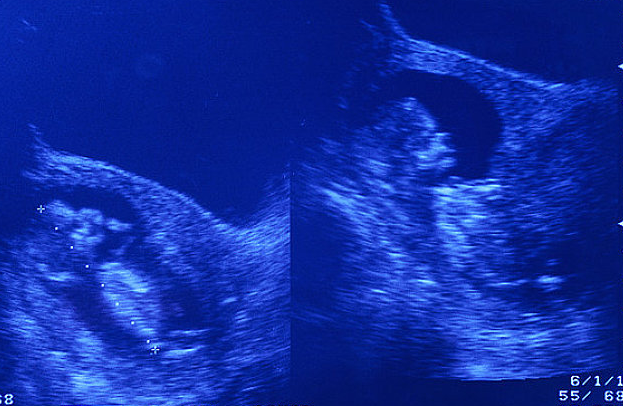

我們知道的妊娠早期最先形成的是孕囊,這也代表著懷孕過程的開始,然后會形成胎芽胎心,這說明受精卵要經歷一個慢慢發展的過程。

一般來說,在孕30-40天左右會形成胎囊,孕40-50天左右會形成胎芽,孕50-60天左右會出現胎心。所以,按常規的胚胎發育來看,我朋友58天沒有胎芽胎心確實可能存在問題。

首先,警惕流血的情況,可能是先兆流產。其次,在沒有腹痛和出血的情況下,孕7、8周可以做一個B超檢查,看看孕囊發育如何,有沒有變皺萎縮的情況。

然后看看有沒有胎芽和胎心,如果10周后還是沒有,那就說明真是胎停育了。最后,也可以做個血檢HCG檢查,看看數值是否符合正常參考值,有沒有下降或過低的情況,然后結合B超檢查結果做出最終判斷。